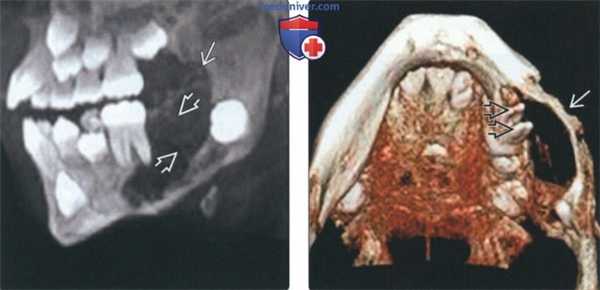

(Слева) На панорамной рентгенограмме визуализируется крупная экспансивная АФО. Обратите внимание на смещение второго моляра нижней челюсти книзу и кальцинаты в виде пончика (отложения эмали и дентина).

(Справа) На аксиальной КЛКТ определяется вздутие лицевой кортикальной пластинки передних отделов верхней челюсти справа, обусловленное АФО. В гиподенсной опухоли находится материал с плотностью зуба.

(Слева) На панорамной реформатированной КЛКТ определяется крупная АФ в задних отделах нижней челюсти, связанная с коронкой формирующеюся непрорезавшегося второго постоянного моляра АФ, содержащая перегородки, выбухает в задние отделы ветви.

(Справа) На трехмерной реконструкции (вид спереди) у этого же пациента визуализируются корни постоянного первого моляра нижней челюсти слева в АФ.